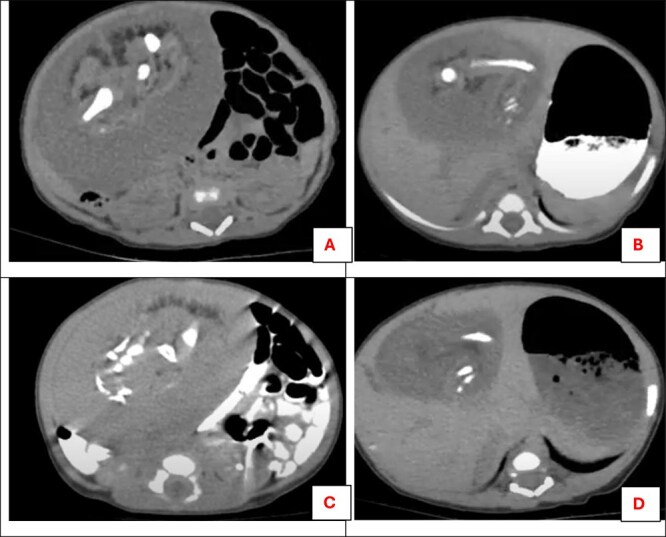

胎中胎(FIF)是一种罕见的先天性异常,涉及双胞胎中的畸形胎儿。它通常表现为出生后发现的无症状腹部肿块,发病率为50万分之一。一个11天大的阿拉伯女婴表现为进行性腹胀。一般体格检查正常。腹部检查发现右上象限有一模糊的固定肿块。影像显示一个8 × 6厘米的腹膜后肿块,内含骨骼元素。经剖腹探查确诊。由于其血管和解剖结构的复杂性,必须仔细解剖。组织病理学检查显示所有三个胚层的组织,不包括畸胎瘤。FIF与畸胎瘤的区别在于脊柱周围组织有组织的发育,通常表现为无恶性潜能。手术切除是可治愈的,复发风险最小。建议长期随访影像学和肿瘤标志物监测并发症,尽管它是良性的。

Fetus-in-fetu (FIF), a rare congenital anomaly, involves a malformed fetus within its twin. It typically presents as an asymptomatic abdominal mass discovered postnatally, with an incidence of 1/500000 births. An 11-day-old Arab female infant presented with progressive abdominal distention. General physical examinations were normal. Abdominal examination revealed an ill-defined fixed lump in the right upper quadrant. Imaging revealed a 8 × 6 cm retroperitoneal mass containing skeletal elements. Surgical exploration via laparotomy confirmed diagnosis. Careful dissection was necessary due to its vascular and anatomical complexity. Histopathological examination revealed tissues from all three germ layers, excluding teratoma. FIF is distinguished from teratomas by the presence of a vertebral column with organized development of surrounding tissues, and typically manifests without malignant potential. Surgical excision is curative, with minimal risk of recurrence. Long-term follow-up with imaging and tumor markers is recommended to monitor for complications, despite its benign nature.